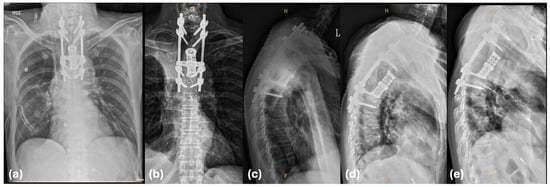

Oligoprogression in NSCLC with Other Actionable Oncogenic Drivers Beyond EGFR and ALK: An Emerging Entity

Oligoprogressive disease (OPD) in non-small-cell lung cancer (NSCLC) is a clinical entity with peculiar behavior and treatment. OPD patients, during systemic therapy, may receive local ablative treatment (LAT) with survival benefit. The importance of OPD and the role of LAT has been comprehensively [...] Read more.

Oligoprogressive disease (OPD) in non-small-cell lung cancer (NSCLC) is a clinical entity with peculiar behavior and treatment. OPD patients, during systemic therapy, may receive local ablative treatment (LAT) with survival benefit. The importance of OPD and the role of LAT has been comprehensively assessed in the setting of EGFR mutant and ALK-rearranged NSCLC during tyrosine kinase inhibitor (TKI) treatment, but it is still almost unexplored in the context of NSCLC harboring actionable oncogenic drivers other than EGFR and ALK. The aim of our review is to collect and discuss the available data about standard treatment in this latter setting, with special consideration given to the role of LAT in case of OPD in systemic treatment. Through a comprehensive PubMed and ClinicalTrials.gov search, we identified the available data and ongoing clinical trials addressing these aims. To date, only limited evidence supports the use of LAT in OPD involving NSCLC driven by these molecular alterations, mainly deriving from case reports and retrospective series. This highlights an unmet clinical need that warrants systematic and multicentric data collection to generate more robust evidence. Full article

Show Figures